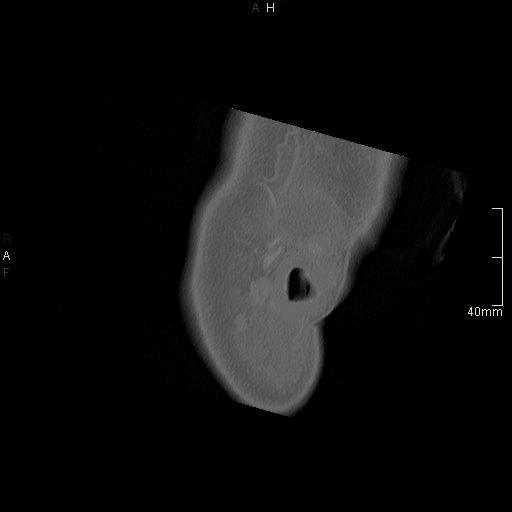

CT Sinuses Contrast- Soft Tissue window (axial)

CT Sinuses Contrast- Bone window (axial)